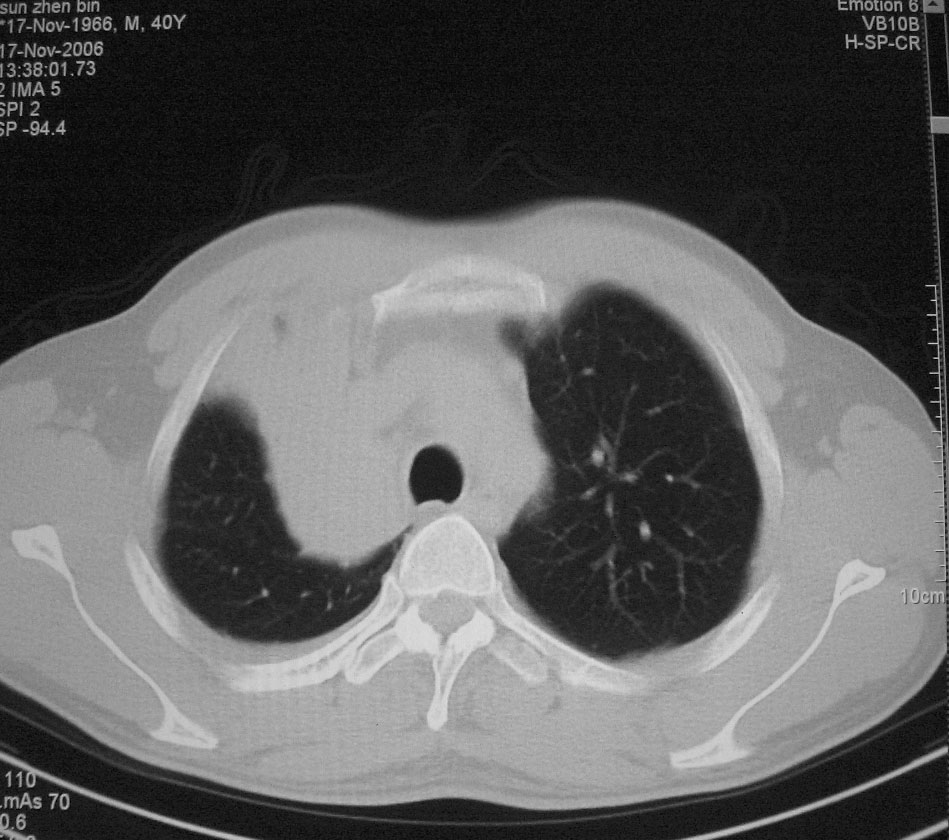

标题: CT5485:[原创]肺部占位请讨论

右肺上叶中央型肺癌并上叶肺不张、纵隔淋巴结肿大

右上叶支气管后壁明显增厚,支持右肺上叶中央型肺癌伴右上叶肺不张、纵隔淋巴结肿大。

右上叶支气管后壁明显增厚,支持右肺上叶中央型肺癌伴右上叶肺不张、纵隔淋巴结肿大。建议支气管镜检查。

右上叶支气管开口变窄,纵隔见肿大的淋巴结。支持右上叶中心型肺癌并右上叶不张纵隔淋巴结肿大。

右肺上叶中央型肺癌并上叶肺不张、纵隔淋巴结肿大.右侧少量胸腔积液。

右肺上叶支气管后壁增厚,呈鼠尾状狭窄,纵隔内未见明显增大的淋巴结影,考虑为中央型肺癌伴右上肺不张